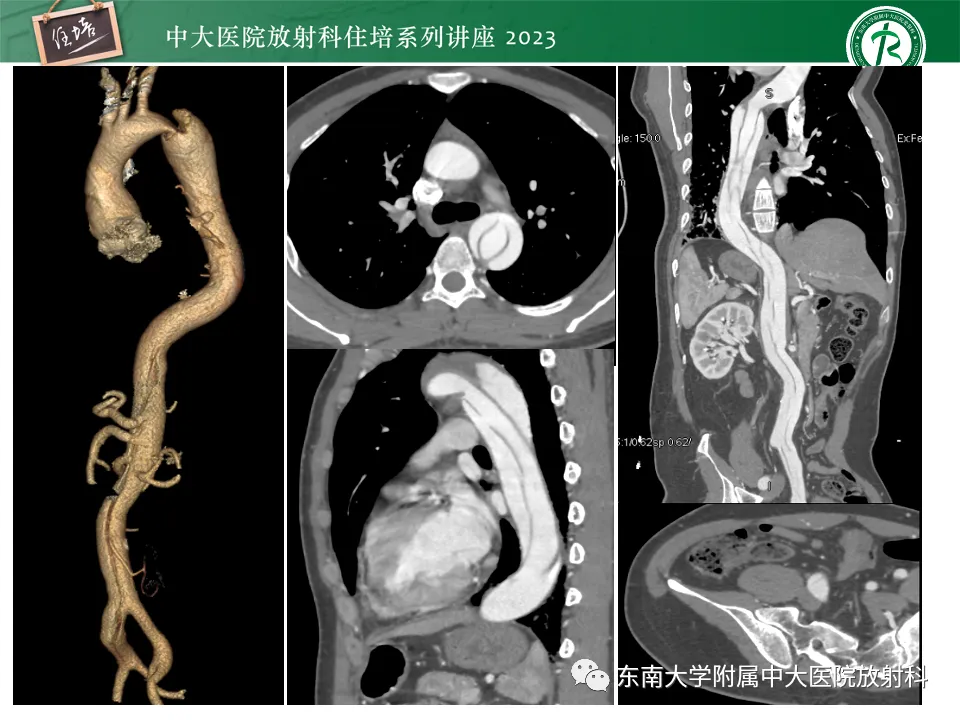

>精美课件丨心脏大血管常见疾病CT图像后处理要点

精美课件丨心脏大血管常见疾病CT图像后处理要点

来源:东南大学附属中大医院医学影像科